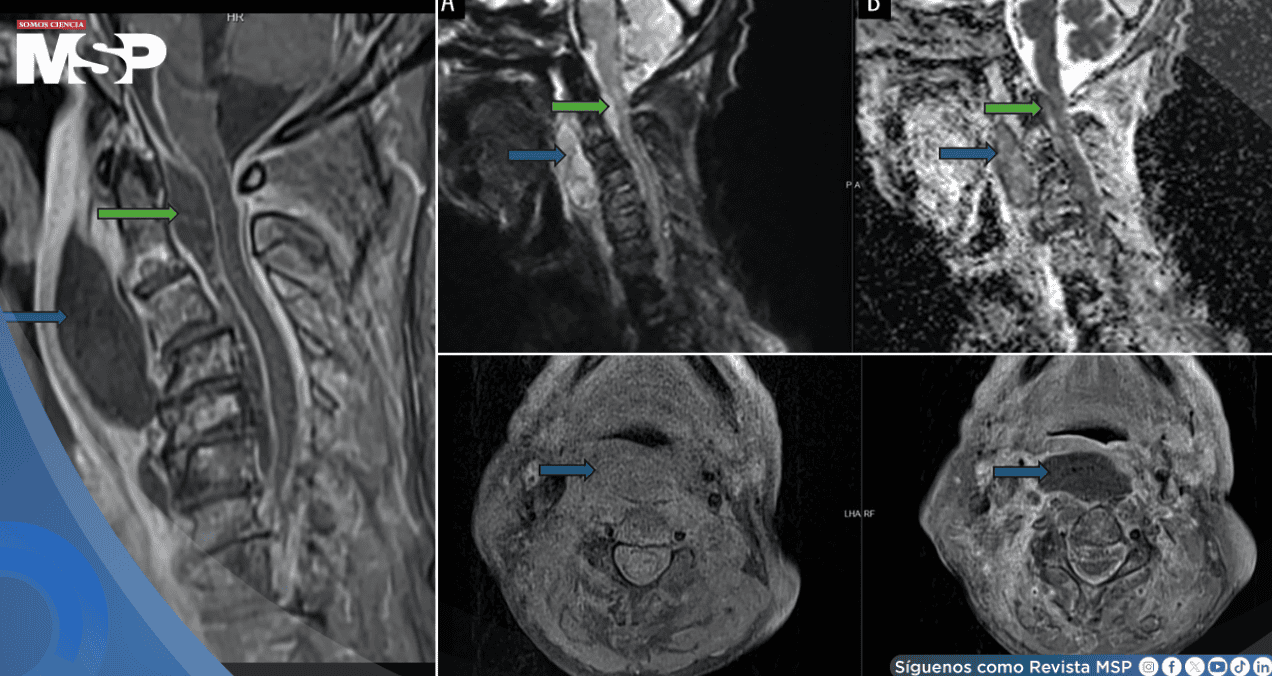

Para determinar la causa precisa de su condición, se realizaron estudios de imagen urgentes. Una tomografía computarizada y una resonancia magnética con contraste de cabeza y cuello revelaron hallazgos alarmantes.

Se observó una inflamación masiva con extenso edema y múltiples colecciones de pus que se comunicaban entre sí. Esta infección afectaba el espacio retrofaríngeo y, de manera crítica, se extendía hacia el espacio epidural en forma de un absceso, comprimiendo la médula espinal a nivel de la unión entre el cráneo y la columna vertebral.